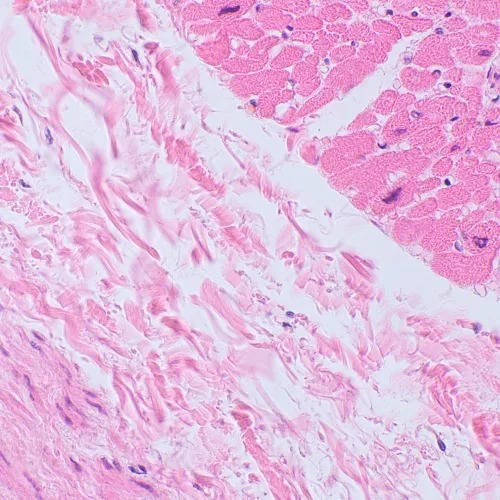

Mikroskop MAGUS Bio 250BL lze použít pro laboratorní práci, vědecký výzkum a výuku studentů. Je určen k pozorování tenkých řezů a stěrů biologických vzorků v procházejícím světle. Hlavní metodou pozorování je světlé pole, ale je možné použít i techniky tmavého pole, polarizace a fázového kontrastu (s dalším příslušenstvím).